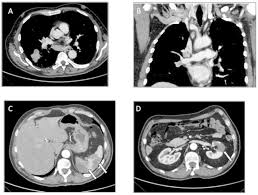

Left Lung Cancer In A Patient With Congenital Unilateral Absence Of The Left Pulmonary Artery A Case Report And Literature Review World Journal Of Surgical Oncology Full Text from media.springernature.com This, in turn, may cause collapse of the air sacs surrounding the tumor. The medical name for these blood clots is a pulmonary embolism (pe). Embolism along central vessels would produce larger areas that would not be mistaken as a nodule because of its characteristic pattern. Pulmonary embolism is commonly misdiagnosed as lung cancer, since sputum cytological tests often show atypical or malignant cells. The severity of pe depends primarily on two factors: At moffitt cancer center, the multispecialty team in our thoracic oncology program ensures a high level of accuracy by offering a full range. Although initially appearing as distinct entities, lung cancer is a great risk factor for the development of pe. Many lung conditions / diseases can cause chest pain, including:

This, in turn, may cause collapse of the air sacs surrounding the tumor. The medical name for these blood clots is a pulmonary embolism (pe). When left undiagnosed and untreated, patients with pulmonary embolism will not survive. Clinical characteristics and outcomes of lung cancer with pulmonary embolism. Lung cancer is the most frequently diagnosed cancer and the leading cause of cancer death among males worldwide.

Pdf Primary Lung Cancer With Growth Into The Lumen Of The Pulmonary Artery from i1.rgstatic.net Lung cancer is the last thing a doctor thinks to look for in young, nonsmoking women, says gerold bepler, m.d., director of the comprehensive lung cancer research center at the moffitt cancer. Sarcoidosis is a rare condition that is often misdiagnosed as malignant tumors due to the similar clinical manifestations and imaging findings. Various organs can be affected including the skin, lymph nodes, and liver. Clinical characteristics and outcomes of lung cancer with pulmonary embolism. Lung cancer is the most frequently diagnosed cancer and the leading cause of cancer death among males worldwide. This means that a doctor. Dvts and pes together are sometimes called venous thromboembolism (vte). This, in turn, may cause collapse of the air sacs surrounding the tumor.